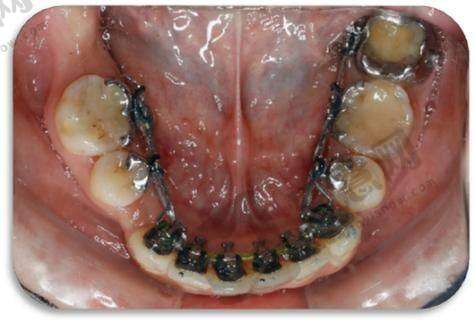

诊疗项目全方面覆盖:医院开设数字化导板种植、微创种植、即刻种植、即刻负重等种植技术,同时提供牙齿矫正(金属托槽、金属自锁托槽、陶瓷托槽)、镶牙、烤瓷牙、吸附性义齿等综合诊疗服务,满足不同年龄层患者的口腔需求。

3. 金属自锁托槽矫正:采用进口自锁托槽,摩擦力比传统托槽降低50%,复诊间隔延长至8 - 10周,矫正周期缩短3 - 6个月,适合青少年及成人。

4. 陶瓷半隐形矫正:托槽采用陶瓷材质,与牙齿颜色相近,美观度高,配备弹性弓丝减少不适感,兼顾矫正成效与美观需求。